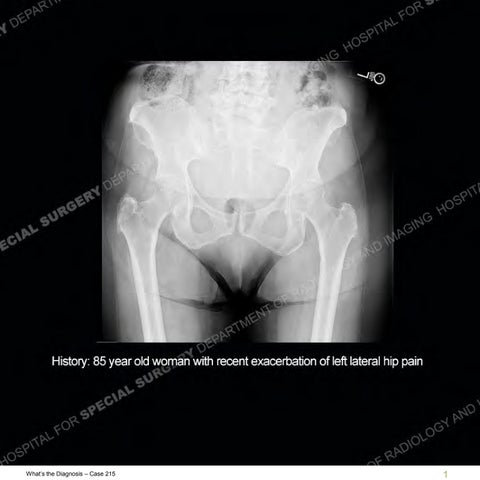

Hospital for Special Surgery is a world leader in orthopedics, rheumatology and rehabilitation. HSS is ranked #1 in the nation for orthopedics. Located in New York City.